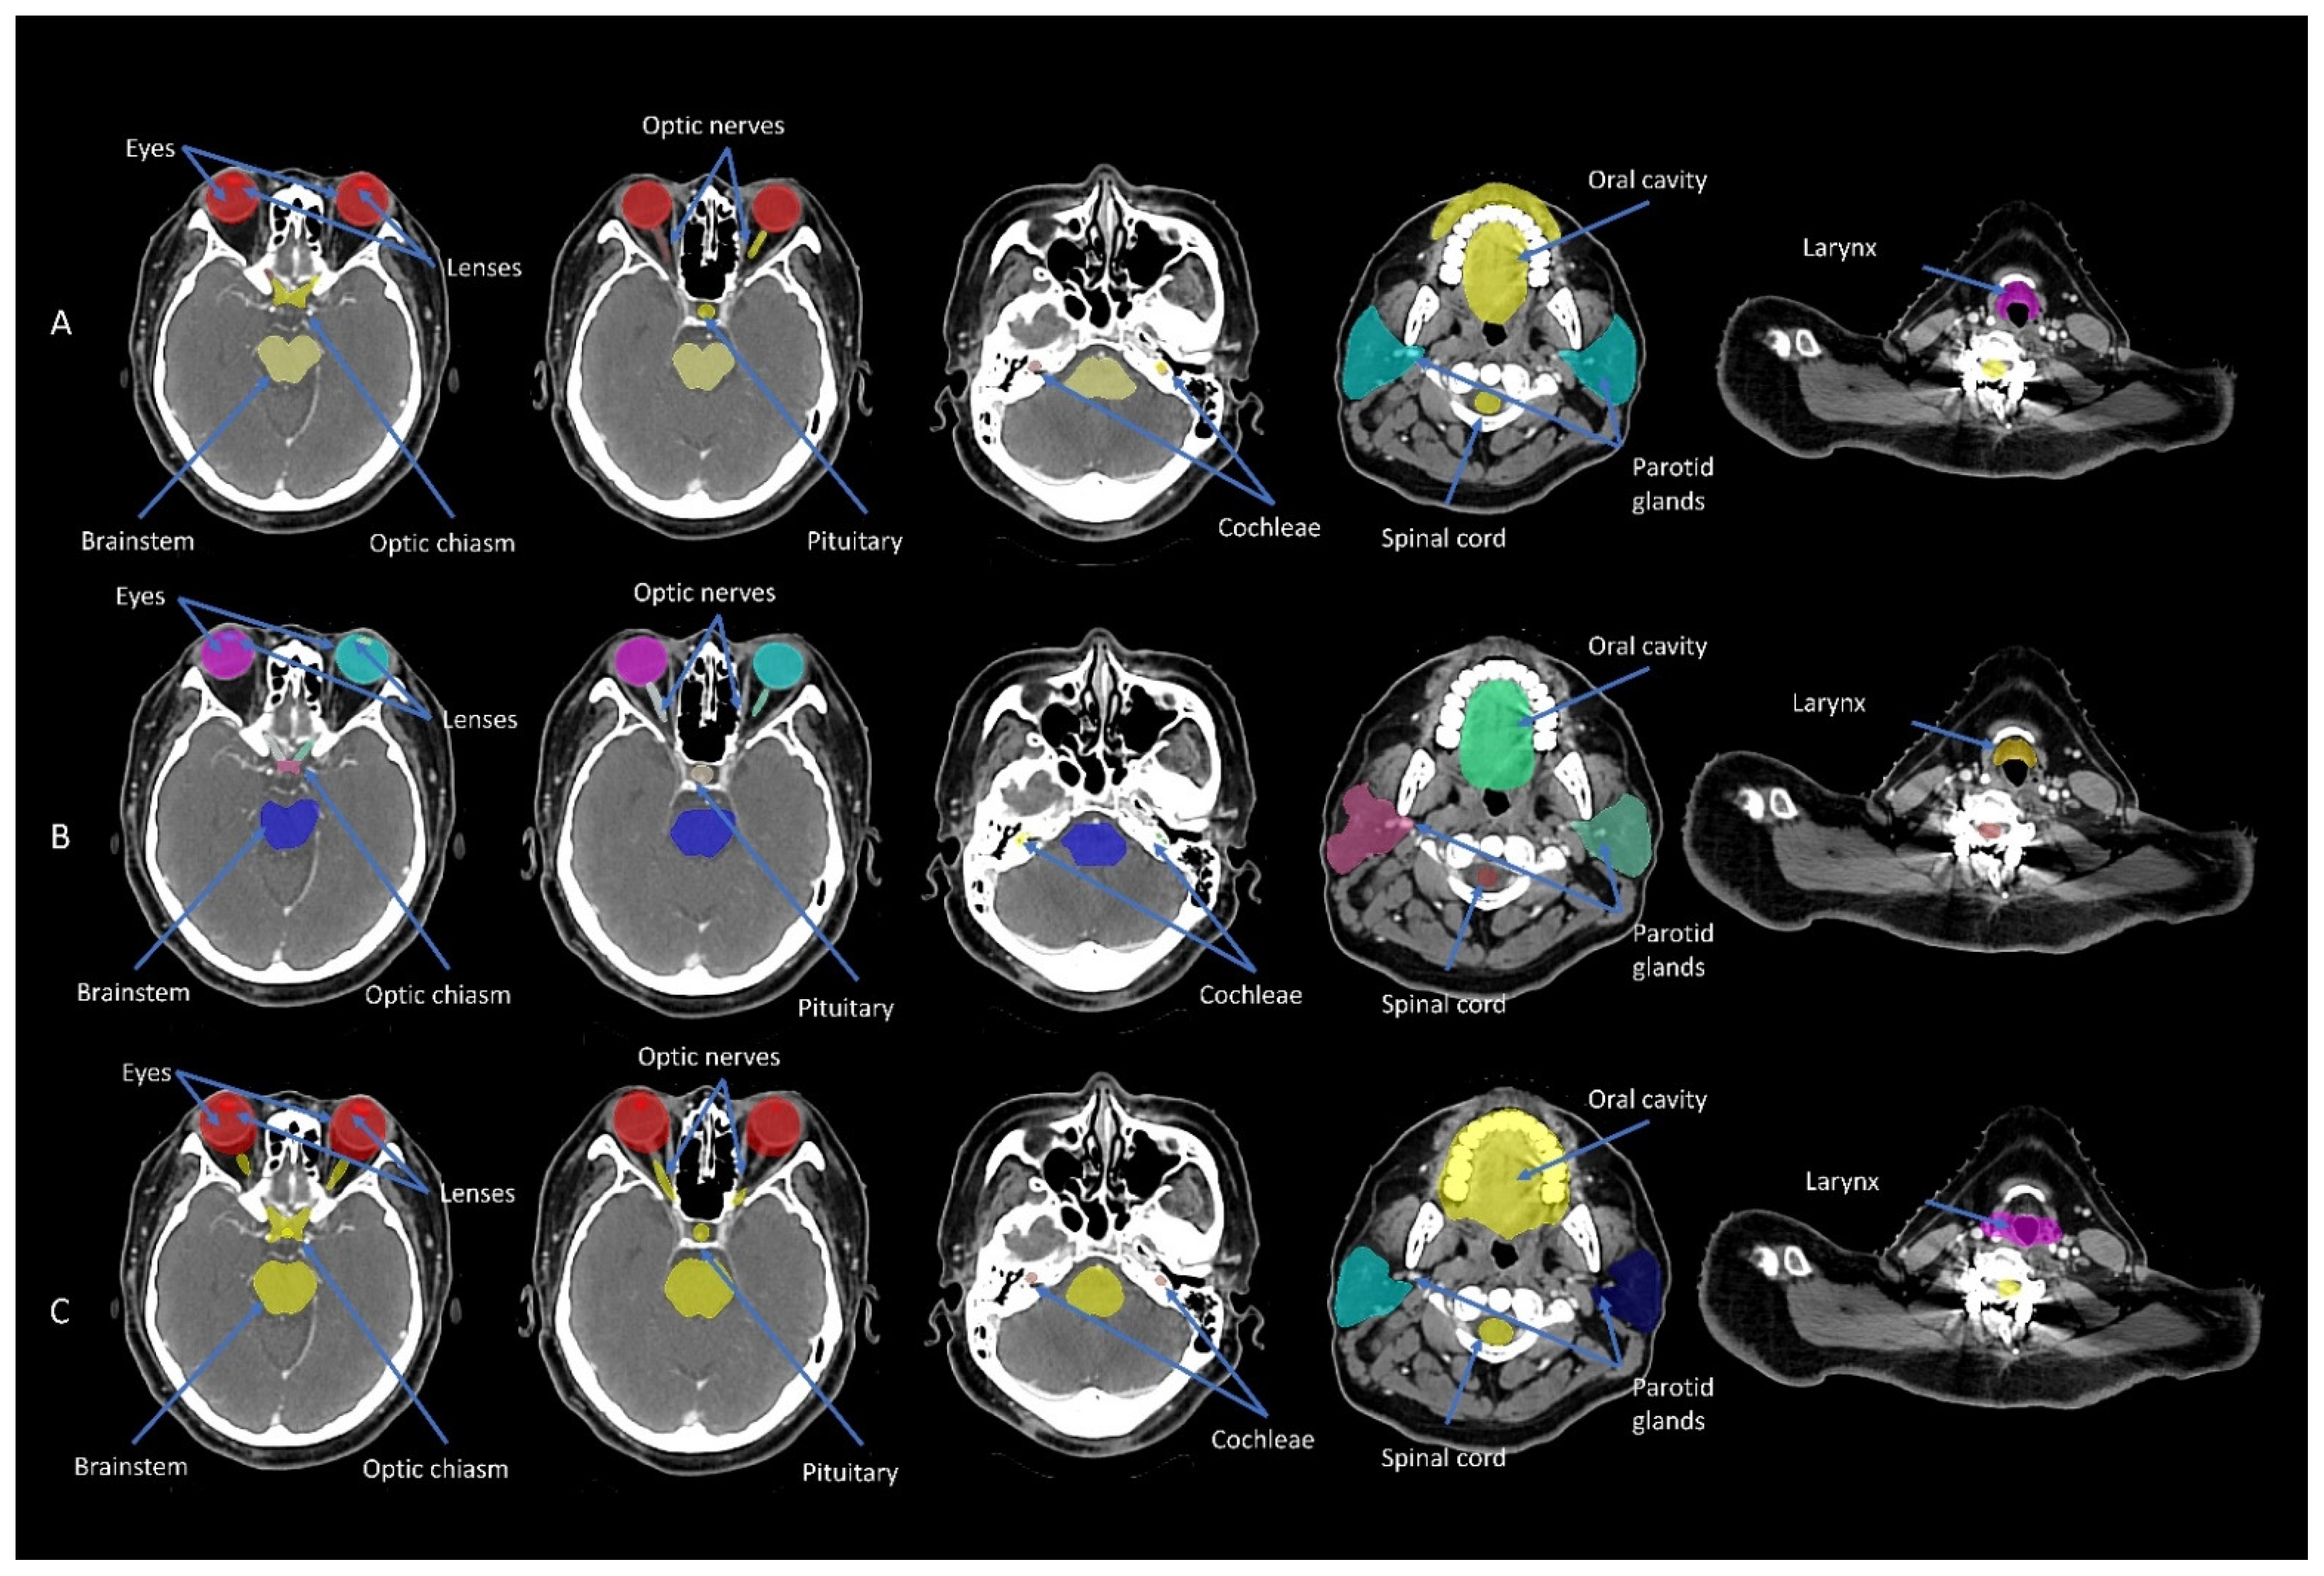

Featured Application

2. Materials and Methods

2.1. Study Design and Imaging Data

2.2. Manual Contouring

2.3. Atlas-Based and DL Auto-Contouring